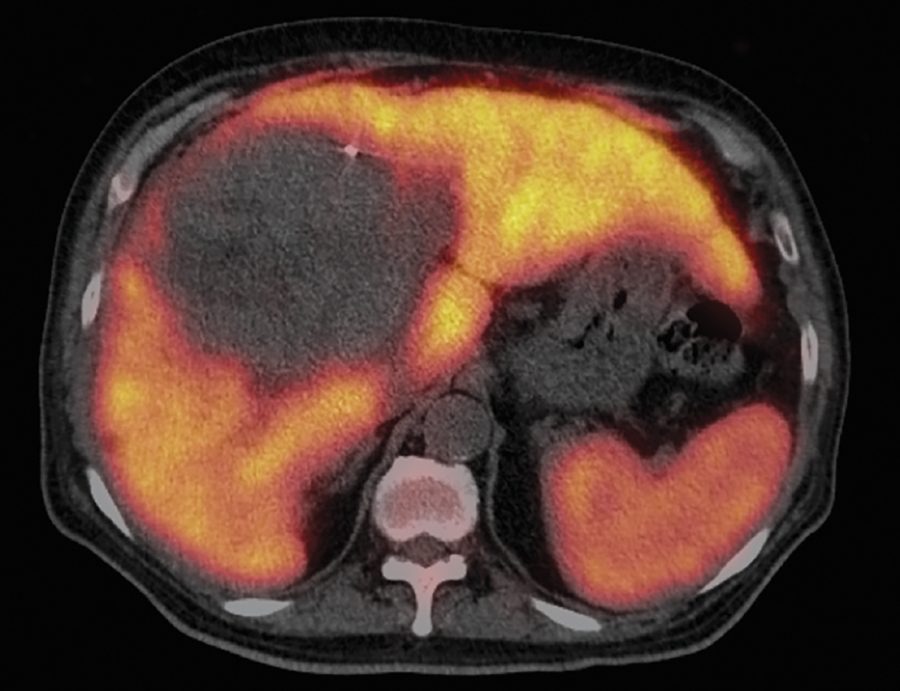

La radioterapia en toda la mama o en la pared torácica y en los ganglios linfáticos mamarios internos puede administrar una dosis de radiación al corazón que aumenta el riesgo de eventos cardiovasculares. Para ver si la terapia de protones puede reducir este riesgo, un ensayo clínico multiinstitucional está comparando la terapia de protones con la radioterapia basada en fotones estándar para pacientes con cáncer de mama localmente avanzado.

Pese a los esfuerzos por reducir la dosis de radiación al corazón, el riesgo de cardiotoxicidad de la radioterapia basada en fotones estándar para el cáncer de mama continúa existiendo. “Con las técnicas que empleamos en el MD Anderson, nuestra dosis con fotones al corazón es más baja que los datos publicados a nivel nacional”, dijo la Dra. Hoffman. “Sin embargo, los protones ofrecen la posibilidad de reducir esa dosis aún más”.

La Dra. Hoffman es la investigadora principal del MD Anderson en el ensayo RAD-COMP en fase III (N.º 2016-0085), que está inscribiendo a pacientes con cáncer de mama con afectación ganglionar que se han sometido a mastectomía o lumpectomía y requieren radioterapia de toda la mama o de la pared torácica y los ganglios linfáticos mamarios internos. “La irradiación de la cadena ganglionar mamaria interna conlleva un alto riesgo de cardiotoxicidad, porque la cadena se extiende precisamente a lo largo del esternón”, dijo la Dra. Hoffman.

El criterio de valoración primario del ensayo corresponde a eventos cardíacos importantes, por los cuales las pacientes recibirán seguimiento durante 10 años. “Podemos observar los planes de tratamiento y acordar que la terapia de protones administra una dosis cardíaca más baja que la terapia estándar”, dijo la Dra. Elizabeth Bloom, profesora del Departamento de Oncología Radiológica y coinvestigadora del ensayo. “Pero es necesario saber si lo que vemos en papel se traducirá en un menor daño cardíaco a largo plazo”.

“Los protones pueden ayudar a mantener la radiación en el lugar correspondiente, y minimizar las dosis al corazón y otras estructuras”, dijo la Dra. Bloom. “Consideramos que esto ofrecerá beneficios para la salud a largo plazo, pero tenemos que probarlo. Ese es el propósito de este ensayo”.